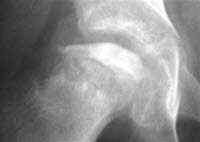

Det vil bli tatt blodprøver av barnet. En røntgenundersøkelse er også nødvendig. De første ukene etter at sykdommen oppstod, kan røntgenbildene være normale. Men etter noen uker vil røntgen kunne vise forandringer i lårbeinshodet og hofteleddet. Tidlig i sykdomsforløpet kan derfor andre undersøkelser være aktuelle. Ultralyd eller MR, eventuelt scintigrafi er også aktuelt.